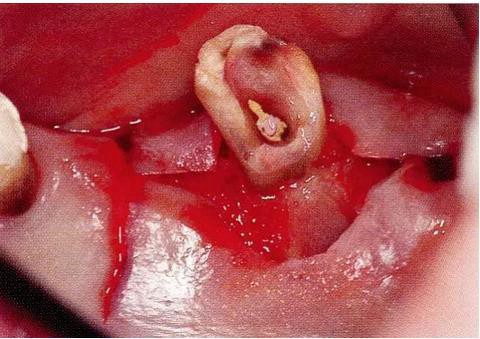

▼圖16-4

圖16-4進(jìn)行牙齒分割時(shí),如圖所示一樣,要確保分割去除的牙根邊緣不會(huì)殘留在牙槽中間骨脊。如果有邊緣殘留,會(huì)造成軟組織發(fā)紅,引發(fā)炎癥。

▼圖17

圖17 將右上6近中頰側(cè)根拔除,考慮到修復(fù)物清潔性的情況下進(jìn)行備牙。牙齒分割后如果有邊緣殘留,就會(huì)使切割面的牙齦發(fā)紅無法治愈。